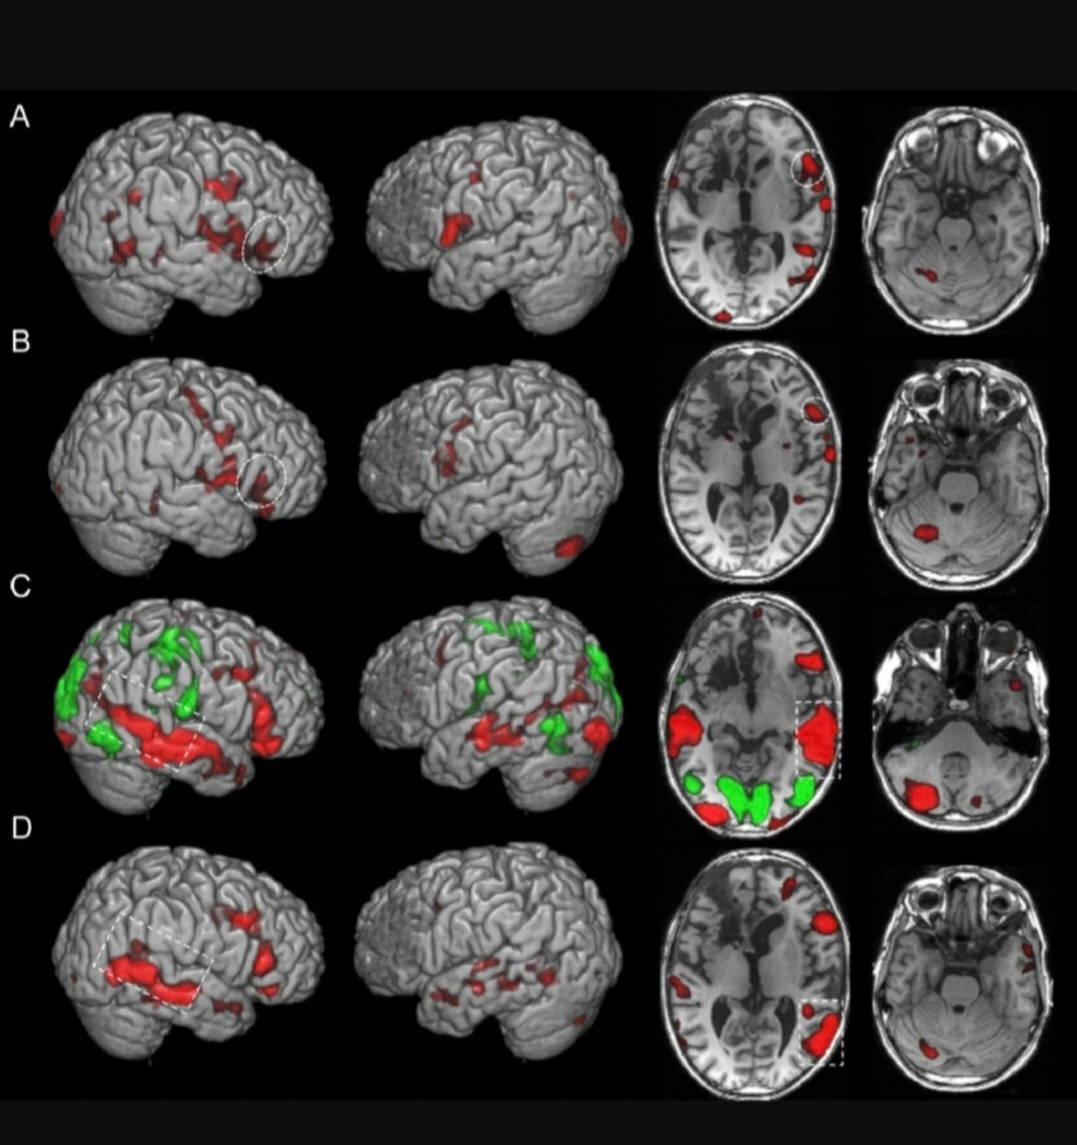

뇌과학 연구를 위해 뇌를 측정할 수 있는 방법 중 하나인 기능자기공명영상법 (functional magnetic resonance imaging, fMRI)으로 찍은 뇌 사진

특히 트라우마, 대인 관계, 우울증 등 깊이 있는 심리적 탐색이 필요한 경우에 정신 분석 치료가 실제적으로 효과가 있음이 임상 연구에서 밝혀져 주목을 받았는데, 따라서 적절한 대상에만 적용된다면 약물 치료 혹은 인지 행동 치료와 복합적으로 사용했을 때 큰 시너지 효과를 보일 것으로 전망되고 있기도 하다

그러나 20세기 후반, 뇌과학이 발전하면서 정신분석학의 고전적인 개념과 현대 뇌과학을 결합하여 인간의 마음을 이해하려는 학문인 "신경정신분석학"의 등장으로 다시 정신분석학은 세간의 관심이 집중되고 있는데, 즉, 과거 정신분석학에서 주목했던 무의식, 상징 등의 심리적 현상을 뇌의 구조와 기능을 통해 밝혀내고자 하는 것이다

기능성 자기공명영상법(functional magnetic resonance imaging, fMRI) 은 혈류와 관련된 변화를 감지하여 뇌 활동을 측정하는 기술이다

특히, 뇌 영상 기술의 발달신경정신분석학 발전에 큰 영향을 미치고 있는데 fMRI, PET 등 다양한 뇌 영상 기술을 활용하여 꿈을 꿀 때, 불안을 느낄 때, 사랑에 빠질 때 등 다양한 심리 상태에서 뇌의 어떤 부위가 활성화되는지 측정이 가능한 상황까지 관련 기술이 발전한 지금, 앞으로 관련 학문의 전망은 무척 아름다울 것으로 예상된다